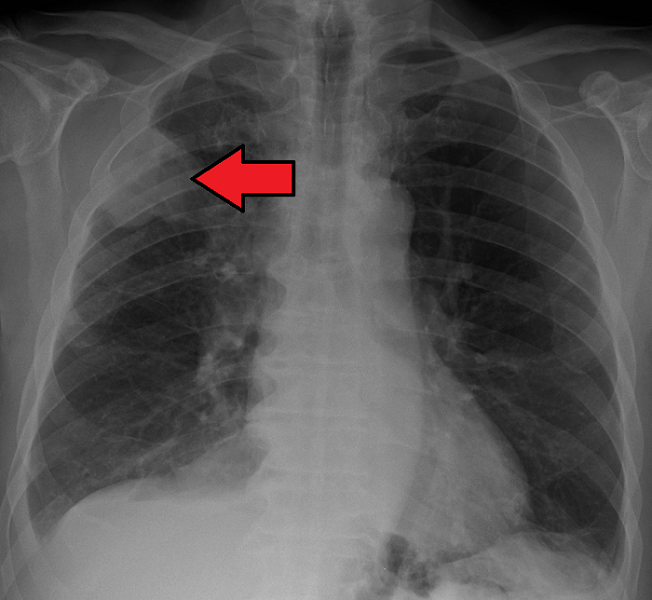

肺癌的X射线。(照片提供詹姆斯海尔曼,MD.)

我是一个被诊断患有4阶段肺癌的退休消防队员。癌症是一种家庭疾病;它会影响你的整个家庭。我使用今天的护理标准治疗,并在一起,我们希望新的治疗方法。癌症研究和护理系统存在问题。研究人员,肿瘤学家和遗传学家告诉我们以下是: